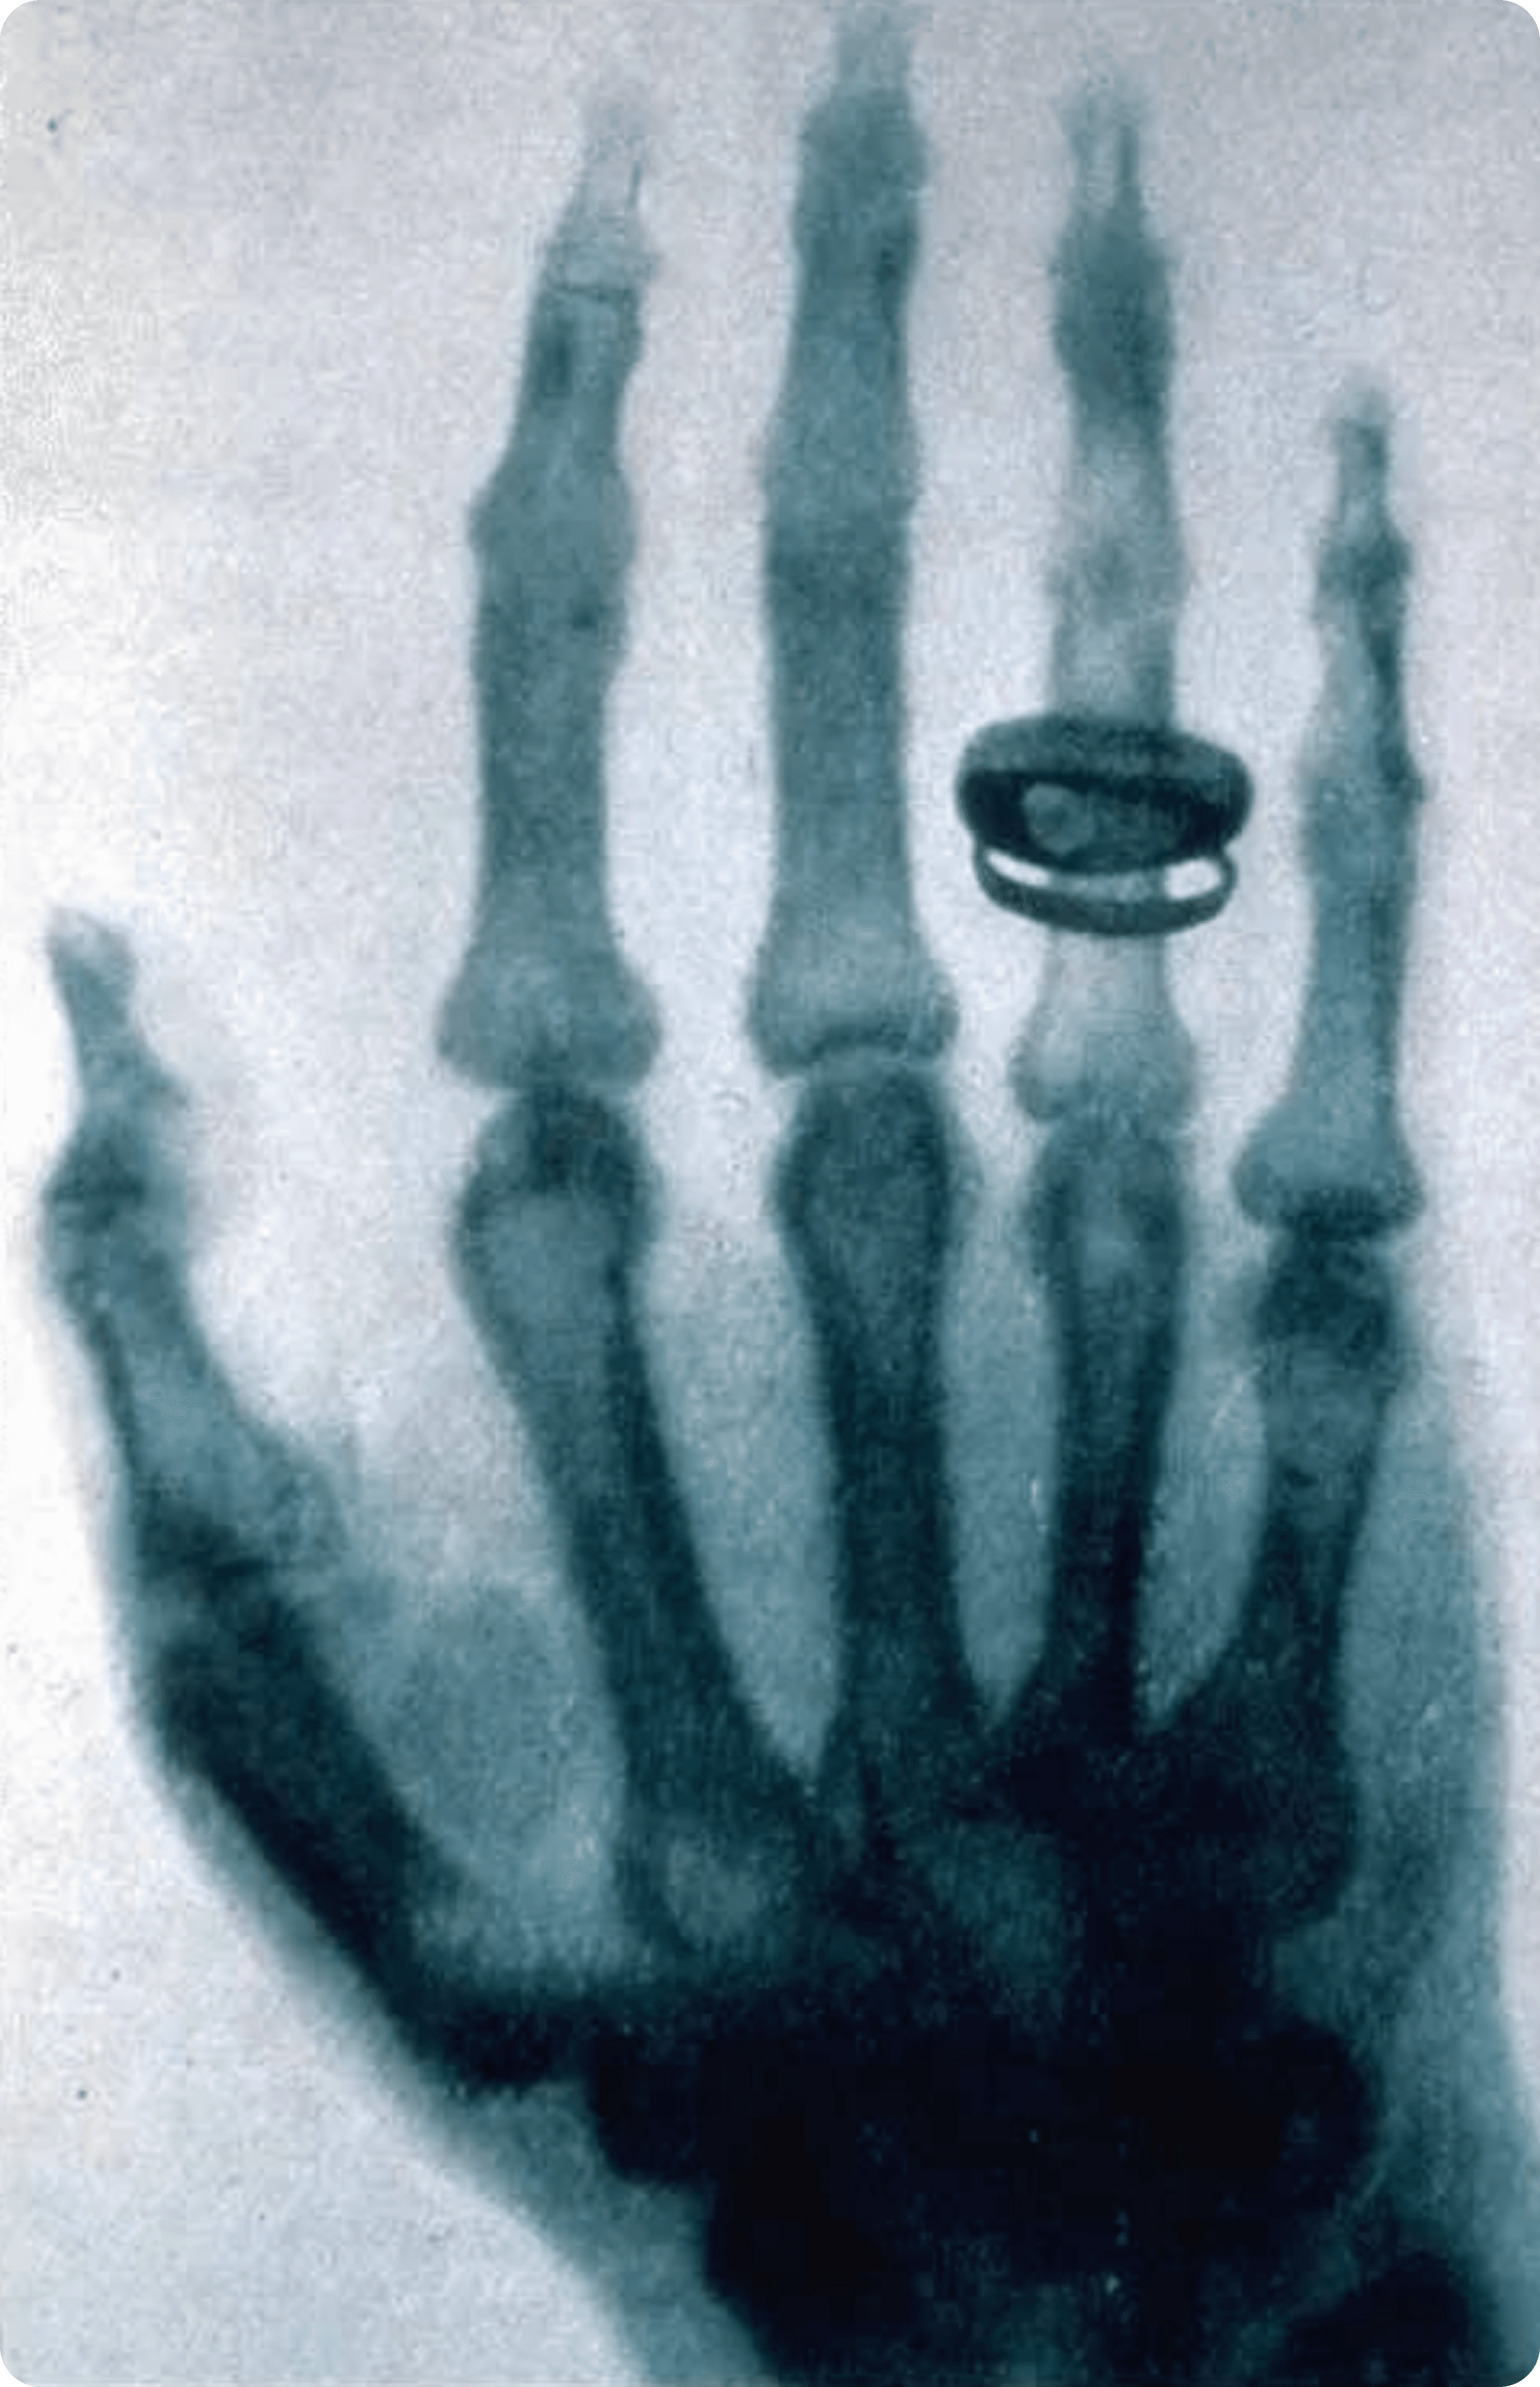

Below is the first X-ray photograph of a human subject:

In the genealogy of modern visual history, the emergence of the X-ray was not merely a technological breakthrough; it was akin to a revolution in the very "mode of seeing". In 1895, when Wilhelm Conrad Röntgen stumbled upon X-rays, humanity was able, for the first time, to penetrate the surface of objects and witness the obscured internal structures — bones, organs, and differences in density. This discovery spread rapidly from the medical field, profoundly shaking the visual convictions held by humanity since the Renaissance: that the world is not solely to be understood through its surface.

Across broader fields, X-ray imagery possesses a unique aesthetic character: matter is no longer distinguished by appearance but rendered through density; contours are not sketched by lines but generated naturally by differences in absorption rates. These translucent, superimposed images strip objects of their weight, yet endow them with a calm and honest order. This visual language naturally strips away ornamentation, pointing instead towards structure, relationship, and essence.